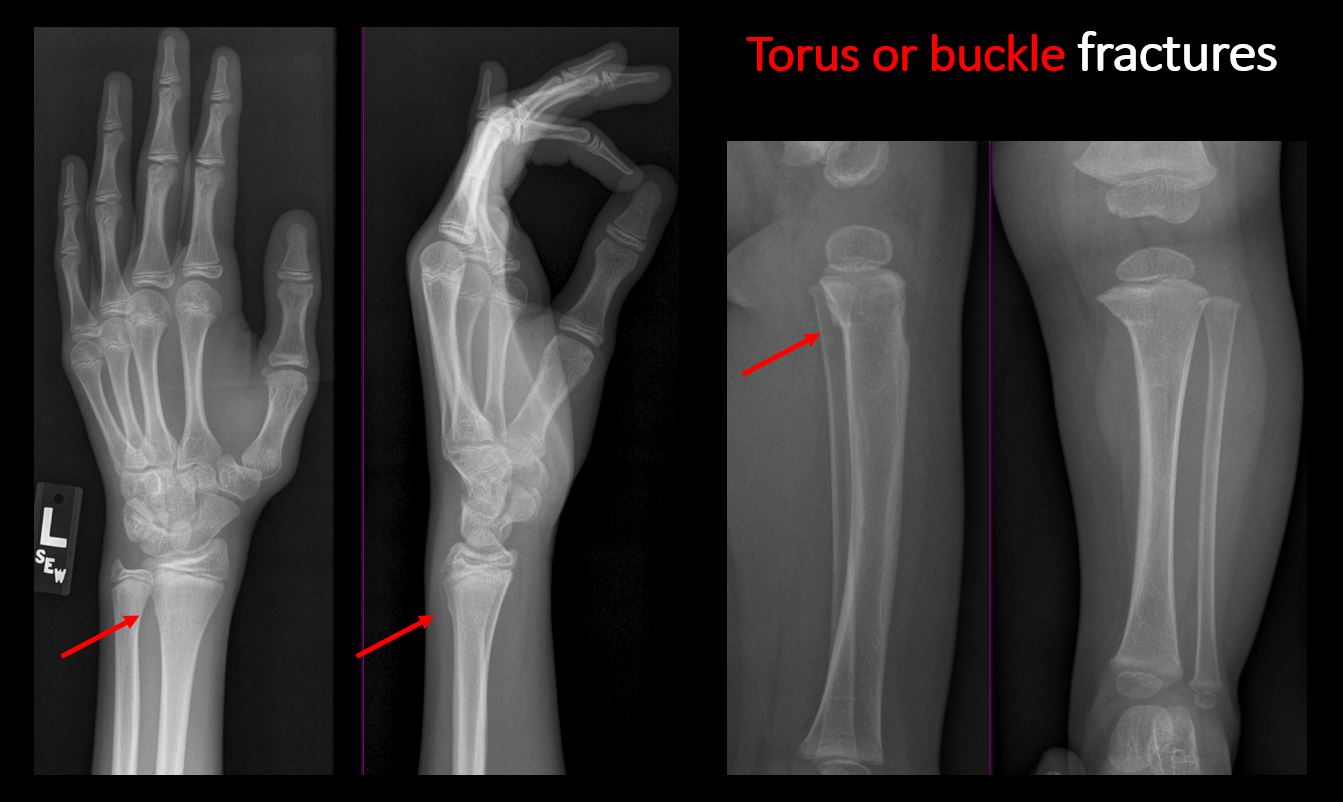

There is abnormal angulation or bulging of the cortical surface relative to the normal cortex which could be from a buckle or torus fracture. |

No | NA |